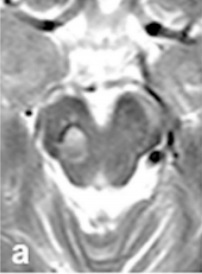

術(shù)后48小時(shí)內(nèi)進(jìn)行了對照MRI檢查。術(shù)后軸位(f)和矢狀位(g) MRI以及術(shù)中照片(h)證實(shí)中腦海綿狀血管瘤完全切除。患者術(shù)后恢復(fù)迅速。

圖:術(shù)后軸位(f)和矢狀位(g) MRI術(shù)中照片

中腦海綿狀血管瘤

圖h:術(shù)中照片證實(shí)中腦海綿狀血管瘤完全切除